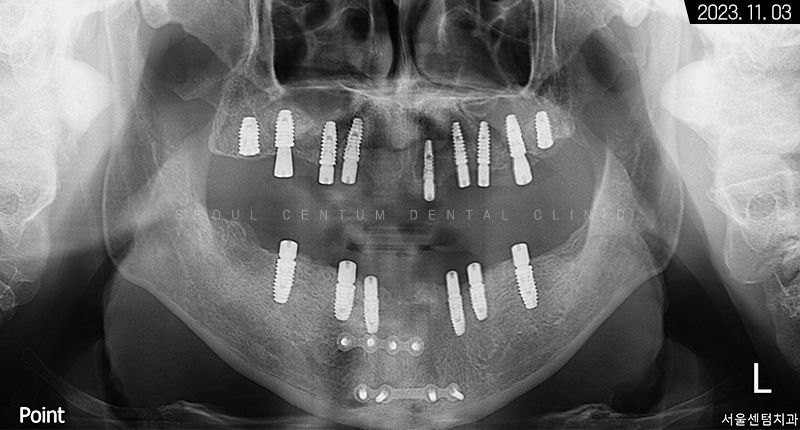

파노라마 엑스레이 사진을 보면 뿌리 주변이 골 소실로 인해 까맣다는 것을 확인할 수 있습니다.

그래서 아래턱을 보존할 수 없는 영구치를 먼저 발치하고 임시 틀니를 사용하면서 저작 기능을 갖기로 했죠. 상악은 픽스처를 고정했고 위턱뼈 어금니 위의 상악동막이 내려왔기 때문에 측방 상악동 거상술도 시행해야 했습니다. 나머지 치조체는 픽스처 고정 위치에 따라 치조정 술식으로 뼈이식재를 넣기로 했습니다.

위턱뼈의 1차 인공 치근 식립을 마치고 나서 3~4개월 후 2차 힐링 어버트먼트를 연결하기로 했으며 동시에 아래턱도 자가골 유도 재생이 어느 정도 진행되었기에 필요시 치조골 이식과 함께 픽스처를 고정해서 1차 수술을 마무리하기로 했습니다.

그렇게 약 9개월의 전체임플란트 기간을 들여서 완성된 모습을 만날 수 있었는데요. 골융합을 높이기 위해 네오 브랜드와 폰틱을 결합하여 사용했습니다.

3개월이 더 지난 후 치근단 사진과 파노라마 엑스레이 사진으로 살펴봐도 초기 임플란트 식립 상황과 동일하게 견고히 자리 잡아 있는 것을 볼 수 있었습니다. 주위염도 생기지 않아 이상적인 결과를 만들어볼 수 있었어요.